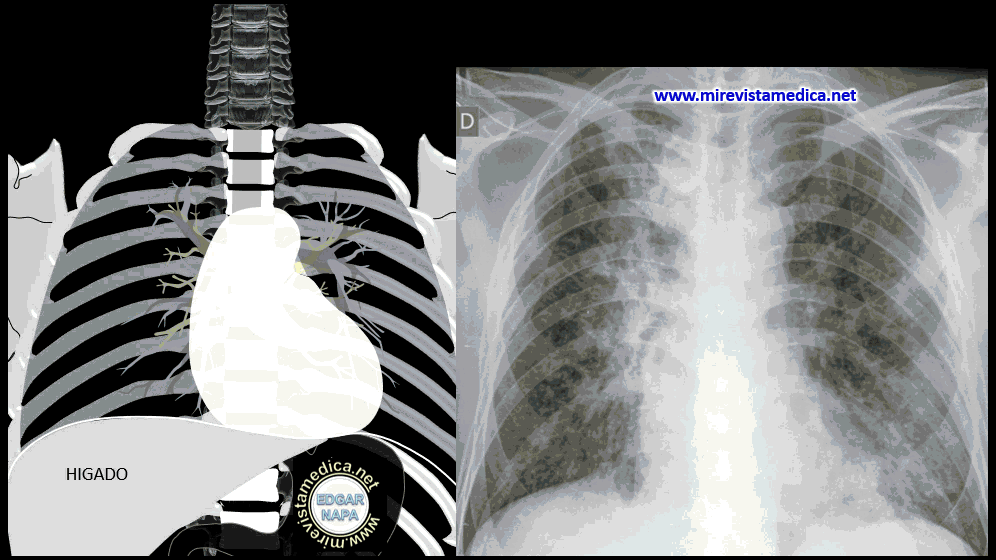

Metástasis del cáncer primario de mama

PATOLOGÍAS DE TORÁX